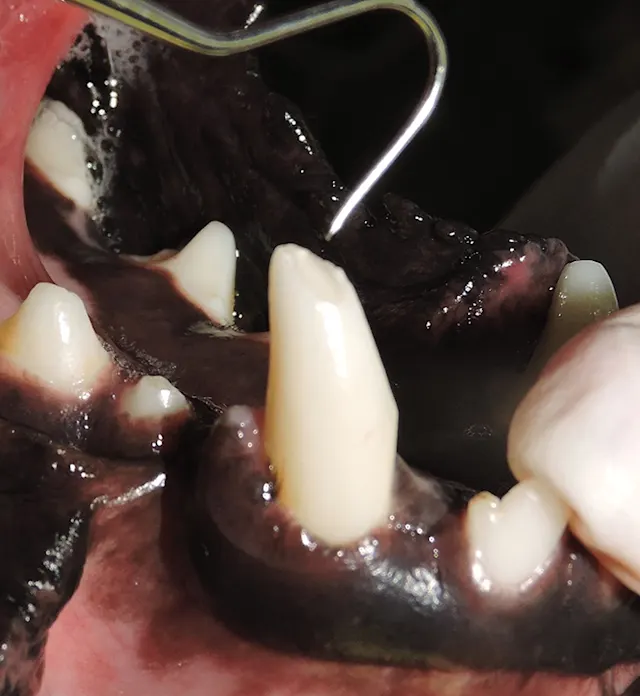

A veterinarian's gloved hand holds a dental scaler while examining the teeth and gums of a dog, revealing signs of gingivitis with red inflammation along the gum line. The setting appears to be a clinical environment focused on dental care for animals.

Figure 9

Observation of a bleeding pulp in a recently fractured tooth could indicate vitality but cannot predict if the pulp will survive the insult.